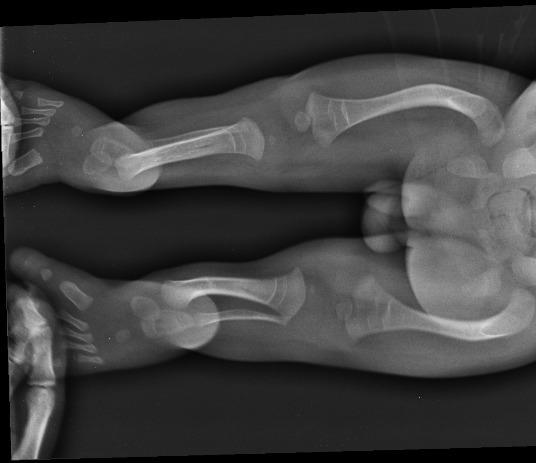

Adam was born on the seventh of October and despite the black visions of doctors he survived more than a few short moments on this Earth. Despite the doctors still strongly claimed that he suffer from osteogenesis imperfecta, we stubbornly proved them that they were wrong. And although they warned us not to hug him, carry on a wooden board, and not to rehabilitate him, groping and guided by our own intuition, we overcame the fear of illness and day by day, from week to week, we were more and more courageous in his care realizing that Adam is not a fragile human being, but a strong and valiant young man, on whom an unjust sentence was given. Our conviction was confirmed by genetic tests that ruled out the brittle bones. Looking for the best specialists in the field of orthopedics, we found Dr. Paley, who was able to correctly diagnose Adam's problem. His legs were never broken but only distorted. An ultrasound picture of pregnancy, as well as X-ray examination, gave the wrong impression of bone after fracture.

Adaś once again proved that he ia a real warrior and began to walk by himself. However, his legs are very curved in many places. Adaś needs a series of operations that will enable him to walk properly, avoid dislocating hips and joints and improve the comfort of his life. His disorder is extremely rare and the series of reconstructions is needed (including straightening femurs, bone of the lower leg, feet reconstruction, hip correction and many other procedures on the so-called soft tissues). After many researches, fate has once again put on our way to Dr. Paley who has his clinic in Florida. The doctor undertook the treatment of Adam to minimize the amount of surgery and thus reduce the amount of pain and suffering to the child. What's more, in our case, he agreed to perform operations in Poland. It is a great chance for us to ensure our son's proper development and in and socializing his peers.